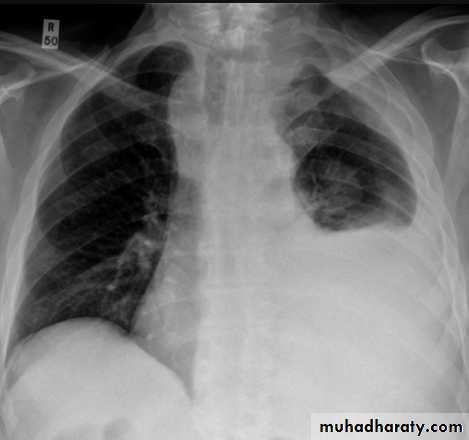

Pleural effusion

Pleural effusion tends to be used as a catch-all term denoting a collection of fluid within the pleural space. This can be further divided into exudates and transudates depending on the biochemical analysis of aspirated pleural fluid. Essentially it represents any pathological process which overwhelms the pleura's ability to reabsorb fluid.Radiographic appearances

Plain radiographChest radiographs are the most commonly used examination to assess for presence of a pleural effusion, however it should be noted that on a routine erect chest x-ray as much as 250-600 ml of fluid is required before it becomes evident 6. A lateral decubitus film is most sensitive, able to identify even a small amount of fluid. At the other extreme, supine films can mask large quantities of fluid.

CXR (erect)

Both PA and AP erect films are insensitive to small amounts of fluid. Features include:

blunting of the costophrenic angle

blunting of the cardiophrenic angle

fluid within the horizontal or oblique fissures

eventually a meniscus will be seen, on frontal films seen laterally and gently sloping medially (note:

A subpulmonic effusion (infrapulmonary effusion) may be seen when there is previously established pulmonary disease, but can also be encountered in normal lungs , They are more common on the right, and usually unilateral

with large volume effusions, mediastinal shift occurs away from the effusion (note: if coexistent collapse dominates then mediastinal shift may occur towards the effusion)